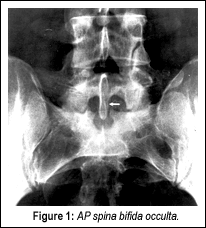

I will demonstrate one case where this was a definite factor in a patient's lower back pain. A 28-year-old male developed lower back pain at the age of 19 while lifting heavy boxes. He had intermittent recurrences of lower back pain since the initial episode. He described the pain as "pins and needles" in the base of his back. The pain radiated to the left hip, with associated intermittent numbness in the left calf. Symptoms were aggravated by standing and physical activity, and were relieved by lying down. He had no pain at night, but did complain of morning stiffness. Neurological examination revealed absent Babinski signs bilaterally, and diffuse, mild tenderness over the lower lumbar spinous processes and paraspinal muscles. Anterior-posterior (Figure 1) and lateral views (Figure 2) demonstrated spina bifida occulta at the S1 segment associated with an elongated L5 SP. Computerized tomography (CT) revealed spina bifida occulta, the classic clasp-knife deformity, with encroachment upon the spinal canal (Figure 3).